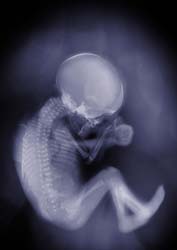

Claro que sí se verían perfectamente los huesos.

Dicho sea de paso a una embarazada jamás le harían una radiografía puesto que la radiación es dañina para el feto.

Si tienes curiosidad, te dejo una imagen de cómo se ve:

¿Cómo pueden pasar los rayos x la piel de la madre y además la del feto? Entonces pueden verse los huesos del feto, es que estoy haciendo un trabajo de la carrera y no encuentro mucha documentación.